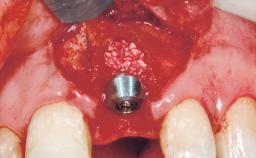

A 30-year-old female patient was referred to the office for the treatment of tooth 11. Her chief concern at the initial visit was to inquire, “Why is my tooth pink?” Upon clinical examination, it was determined that tooth 11 had a previous history of trauma and that the clinical crown had become noticeably pink in color as a result of internal resorption. This diagnosis was confirmed radiographically, indicating a large radiolucency involving the central and distal portions of the clinical crown. It was determined that restoration of this tooth was not possible, and that extraction was indicated. The presence of a mid-line diastema, which the patient wanted to reproduce, directed the treatment plan for tooth replacement utilizing a dental implant.

| Placement Protocol | Immediate implant placement |

| Socket Morphology | Single-root socket |

| Socket Integrity | Sufficient, with intact bone walls |

| Bone Volume | Sufficient, with intact walls |

| Bone Augmentation | Horizontal|Simultaneous |

| Augmentation Materials | Autogenous chips|Membrane |